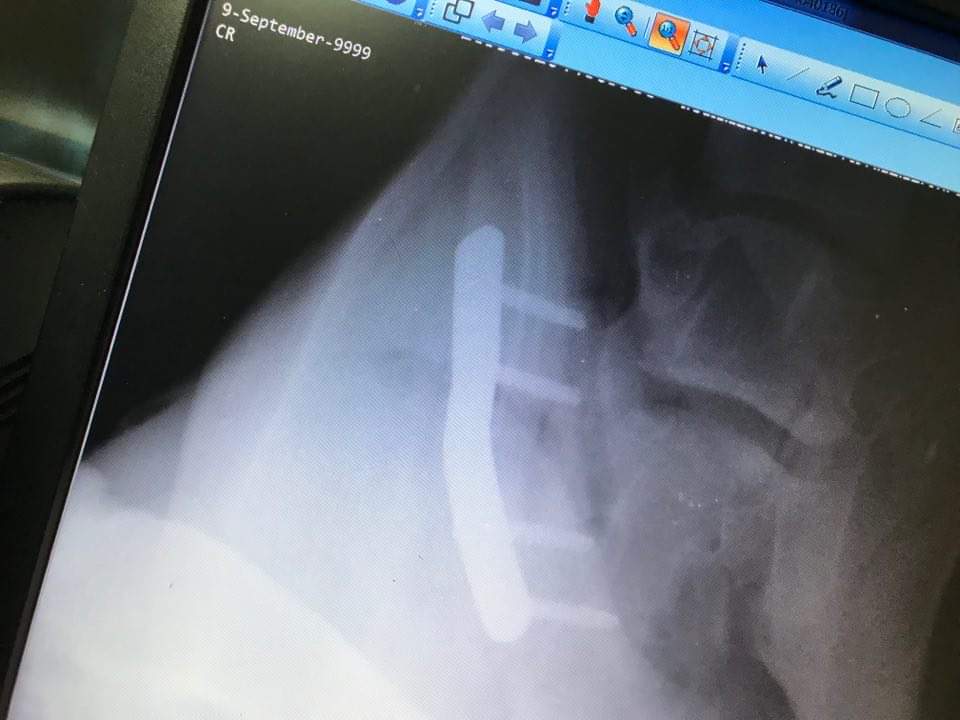

Verletzungen, Operationen

Leider sind diese Dinge immer wieder nötig! Erschreckende Bilder!